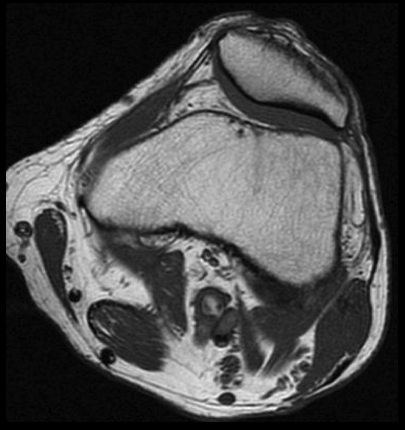

SE T1 AXIAL

3. Para confirmar los hallazgos de la angioTC de extremidades inferiores, se realizó RM de rodilla izquierda. ¿Qué hallazgo se observa en la secuencia axial SE T1?

- A. Aneurisma poplíteo trombosado.

- B. Quiste adventicial en la pared de la arteria poplítea.

- C. Banda muscular anómala rodeando a la arteria poplítea.

- D. Exóstosis de tibia comprimiendo la arteria poplítea.

- E. Flap intimal intraluminal.